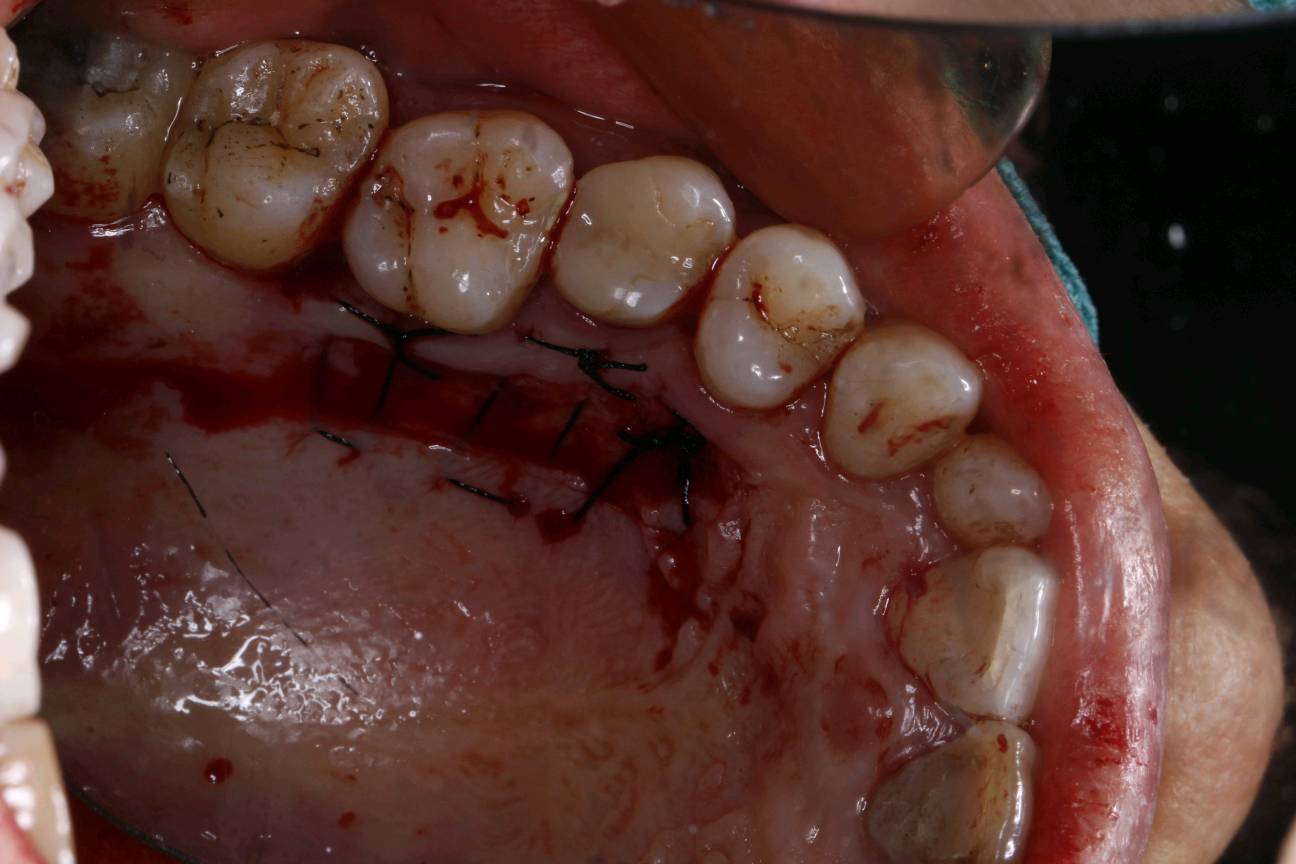

患者女30岁,左下后牙缺失已植入种植体,牙槽嵴呈刀刃壮,附着龈明显不足。角化牙龈缺乏易造成种植体抗炎屏障变弱,容易导致软组织炎症和边缘骨水平吸收。建议患者做游离牙龈移植术。通过获取自体健康游离龈瓣,移植到角化不足的患区,使种植体周围角化组织宽度增加,前庭沟加深。成功的话,会有良好的预后效果。